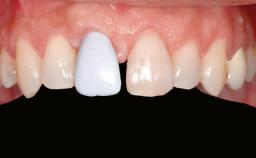

Shell Technique for Horizontal and Vertical Maxillary Bone Augmentation in a Partially Edentulous Patient with Aggressive Periodontal Disease

A 46-year-old woman was referred for treatment whose main complaints were mobility of her fixed partial dentures (right maxilla and left mandible) and periodontal bleeding during function. She also reported having taken systemic antibiotics to treat recurrent swelling in the area of the upper left molars. The patient had not seen a dentist for at least 2 years. She did not smoke and had no history of major systemic disease other than two minor orthopedic procedures some years back. The first-visit examination revealed poor plaque control, tooth mobility, periodontal disease, and a residual dentition widely associated with deep periodontal pockets.

Prosthesis Type FDP